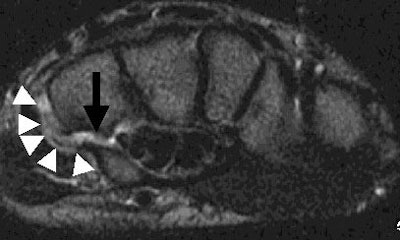

| The axial, proton density MR image above demonstrates an oblique fracture through the base of the hook of the hamate (black arrow). The sclerosis at the margins of the picture is consistent with the clinical report of old trauma. |

| Above, an axial T2-weighted MR image shows the oblique fracture through the base of the hook of the hamate with intervening fluid (black arrow). The increased T2 signal, indicative of edema and inflammation (white arrowheads) corresponded to the location of the patient's pain. |